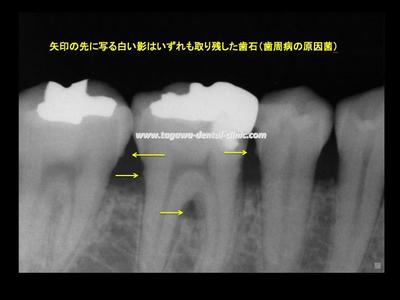

ところが―― これまで「長期間歯周病治療を受けていた」と伺っていたにもかかわらず、 歯ぐきの中には大量の歯石が残ったままでした。

「歯石を取らずに光殺菌だけ繰り返していた...?」 疑問に感じ、光治療について最新文献を調べ直しました。